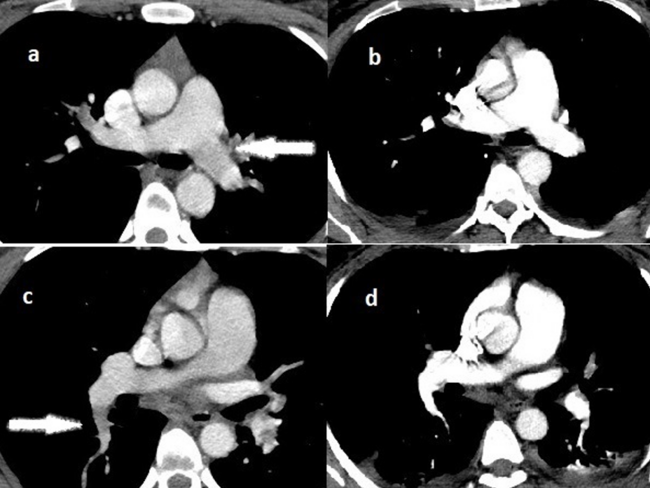

A computed tomography (CT) pulmonary angiography examination was performed immediately because of suspected PE. CT acquisitions were performed with multidetector CT units on a 128-slice CT scanner (Philips Ingenuity Core128, Philips Medical Systems) using standard protocols. A CT pulmonary angiogram revealed extensive bilateral pulmonary thrombosis, primarily involving the proximal aspect of both main pulmonary arteries (Figure 1A and C). Fat embolism was ruled out. Following the diagnosis of PE, treatment with 50 mg alteplase tPA (Actilyse; Boehringer Ingelheim) was administered over 2 hours intravenously.

The patient had an adequate response to systemic thrombolysis. After the tPA infusion, oxygenation and blood pressures improved. The ratio of PaO2 to fractional inspired oxygen (FiO2) increased to 80 (PaO2 of 75 mm Hg and FiO2 of 93%) on the following day. Laboratory studies showed the patient's d-dimer level had decreased from >10000 ng/mL before treatment to 2653 ng/mL on the following day of thrombolysis. A posttreatment control CT revealed that the thrombi were successfully lysed (Figure 1B and 1D). The patient bled through abdominal drains and received an erythrocyte suspension transfusion along with 5 units of packed red blood cells and 3 units of fresh-frozen plasma over the course of 48 hours. On postoperative day 3, the bleeding had stopped and the drains were removed. The patient was discharged on rivaroxaban therapy for 6 months.